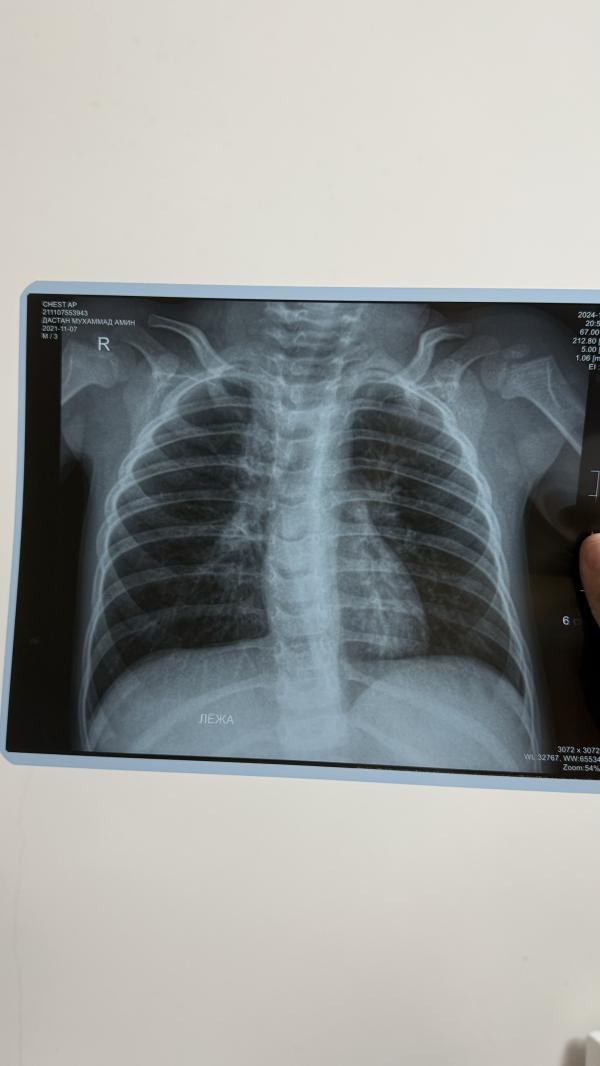

Пы сы , мы были у пульмонолога это пневмония. Просто хочу проверить ИИ

Да односторонняя пневмония

Я написала, чтобы он угадал что мог сказать врач. Вот что пишет:

читывая предыдущие сообщения, возможно, врач сказал что-то вроде:

"На снимке не видно явных признаков бактериальной пневмонии, но это не исключает её полностью. Основываясь на анализах и симптомах, наблюдается лёгочное воспаление, которое может требовать лечения. Рекомендую продолжить наблюдение и при необходимости провести дополнительные исследования, такие как КТ, чтобы уточнить диагноз."

Это стандартный подход в случаях, когда симптоматика и результаты не дают чёткой картины на рентгене.